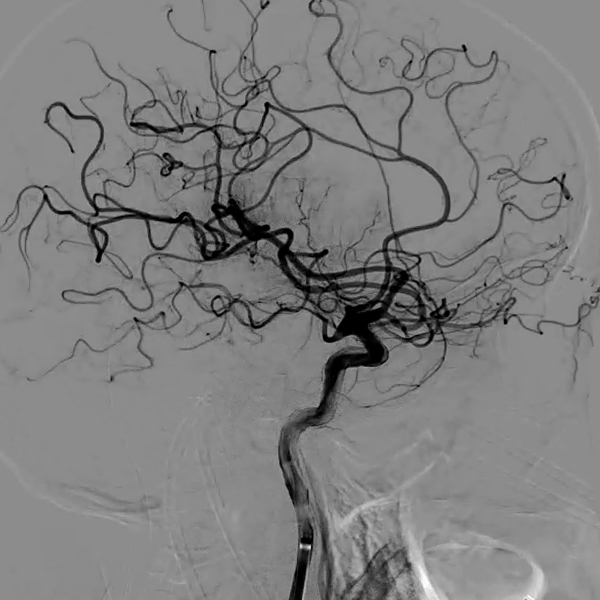

Entrevista al neurorradiólogo intervencional Dr. Ignacio Molina, Unidad Neurovascular HGGB

Desde el área de la neurorradiología intervencional, el HGGB cuenta con técnicas endovasculares que permiten tratar lesiones y prevenir complicaciones mayores.

• Aneurismas intracraneales: si se detectan antes de romperse, pueden ser tratados para evitar hemorragias.

• Hemorragias cerebrales: cuando un aneurisma roto provoca sangrado, es posible intervenir para prevenir un resangrado, que tiene alta mortalidad.